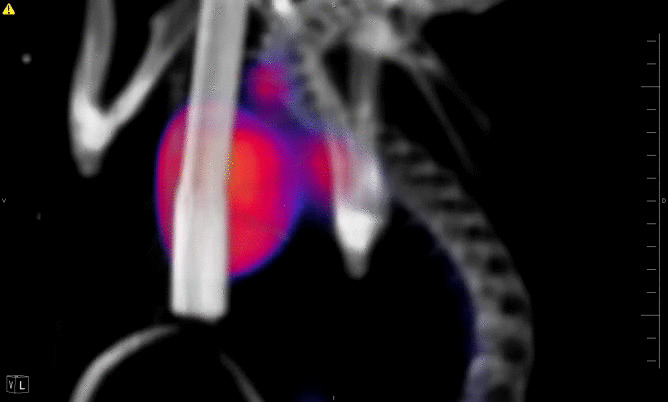

Recent advances in whole mouse imaging using PET/CT

PET/CT of Pulmonary Y. pestis mouse - Drs. Guo and Lawrenz

Animated image of PET/CT showing heart only

Animated image of PET/CT showing heart and bone structure

Animated image of PET/CT showing heart, lungs and bone structure